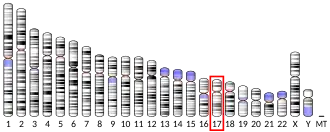

There are two types of orexin: orexin-A and orexin-B (hypocretin-1 and hypocretin-2).[17][18] They are excitatory neuropeptides with approximately 50% sequence identity, produced by cleavage of a single precursor protein.[17] This precursor protein is known as prepro-orexin (or preprohypocretin) and is a 130 amino acid pre-pro-peptide encoded by the gene HRCT and located on chromosome 17 (17q21).[19] Orexin-A is 33 amino acid residues long and has two intrachain disulfide bonds; orexin-B is a linear 28 amino acid residue peptide.[17] Although these peptides are produced by a very small population of cells in the lateral and posterior hypothalamus, they send projections throughout the brain. The orexin peptides bind to the two G-protein coupled orexin receptors, OX1 and OX2, with orexin-A binding to both OX1 and OX2 with approximately equal affinity while orexin-B binds mainly to OX2 and is 5 times less potent at OX1.[20][21]